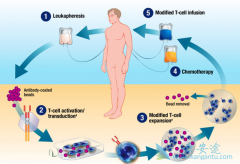

CD22 CAR-T疗效如何 ?研究共纳入15例儿童ALL患者,都属于对化疗耐药的患者,其中四例患者为造血干细胞移植后复发的。研究结果显示,CD22 CAR-T细胞治疗缓解率很高,完全缓解(CR)率为80%,1例患者为部分缓解(PR),所以整体反应率为86.7%。14例患者CD ...

按照基因突变, 弥漫性大B细胞淋巴瘤 (DLBCL)可分成4种亚型,包括MCD亚型、N1亚型、BN2亚型以及EZB亚型。CAR-T细胞疗法也是第四届上海国际淋巴肿瘤高峰论坛的重要内容,多名研究者公布了CAR-T的相关研究结果,CAR-T也是近几年免疫治疗领域的热点话题。目 ...

为了提高 CAR-T 在体内存留时间、扩增能力和形成记忆细胞的能力,研究人员尝试对不同信号通路进行调控。 如AKT分子活化驱动了效应细胞的分化,削弱了细胞存活和分化成记忆细胞的能力,从某种程度上影响了 T 细胞记忆和保护性免疫的作用。在第57届ASH上有 ...

CAR-T疗法 目前最主要的问题是可能引起细胞因子风暴。为此,FDA已经扩大了罗氏旗下的类风湿性关节炎(RA)药物托珠单抗(Actemra)适应症,目前可以用于由CAR-T细胞治疗引起的细胞因子释放综合征,也就是我们常说的细胞因子风暴的治疗。 尽管嵌合抗 ...